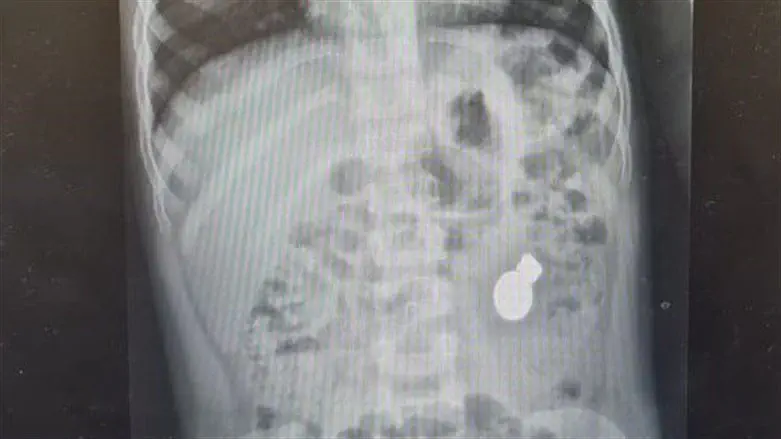

בצילום מעי שנעשה לשרה עם הגעתה למיון, ד"ר מרדכי סליי, רופא בכיר במחלקת ילדים ומנהל יחידת גסטרואנטרולוגיה התערבותית, הבחין בשקל עליו סיפרה הפעוטה, אך בנוסף אליו גם בשני מגנטים.

"לפי הצילומים ולפי מעקב קפדני שערכנו לשרה, ראינו שהמגנטים והשקל לא מתקדמים ולא זזים. זה העלה לנו חשד שהמגנטים ממגנטים אחד את השני וגם את השקל ובעצם כולאים כך את המעיים ומונעים מהם לזוז. אירוע שכזה עלול לגרום לנמק, פצע לחץ, שיכול לעשות חור במעי, ואז יהיה כמובן מדובר במצב קשה ומסכן חיים" מסביר ד"ר סליי.